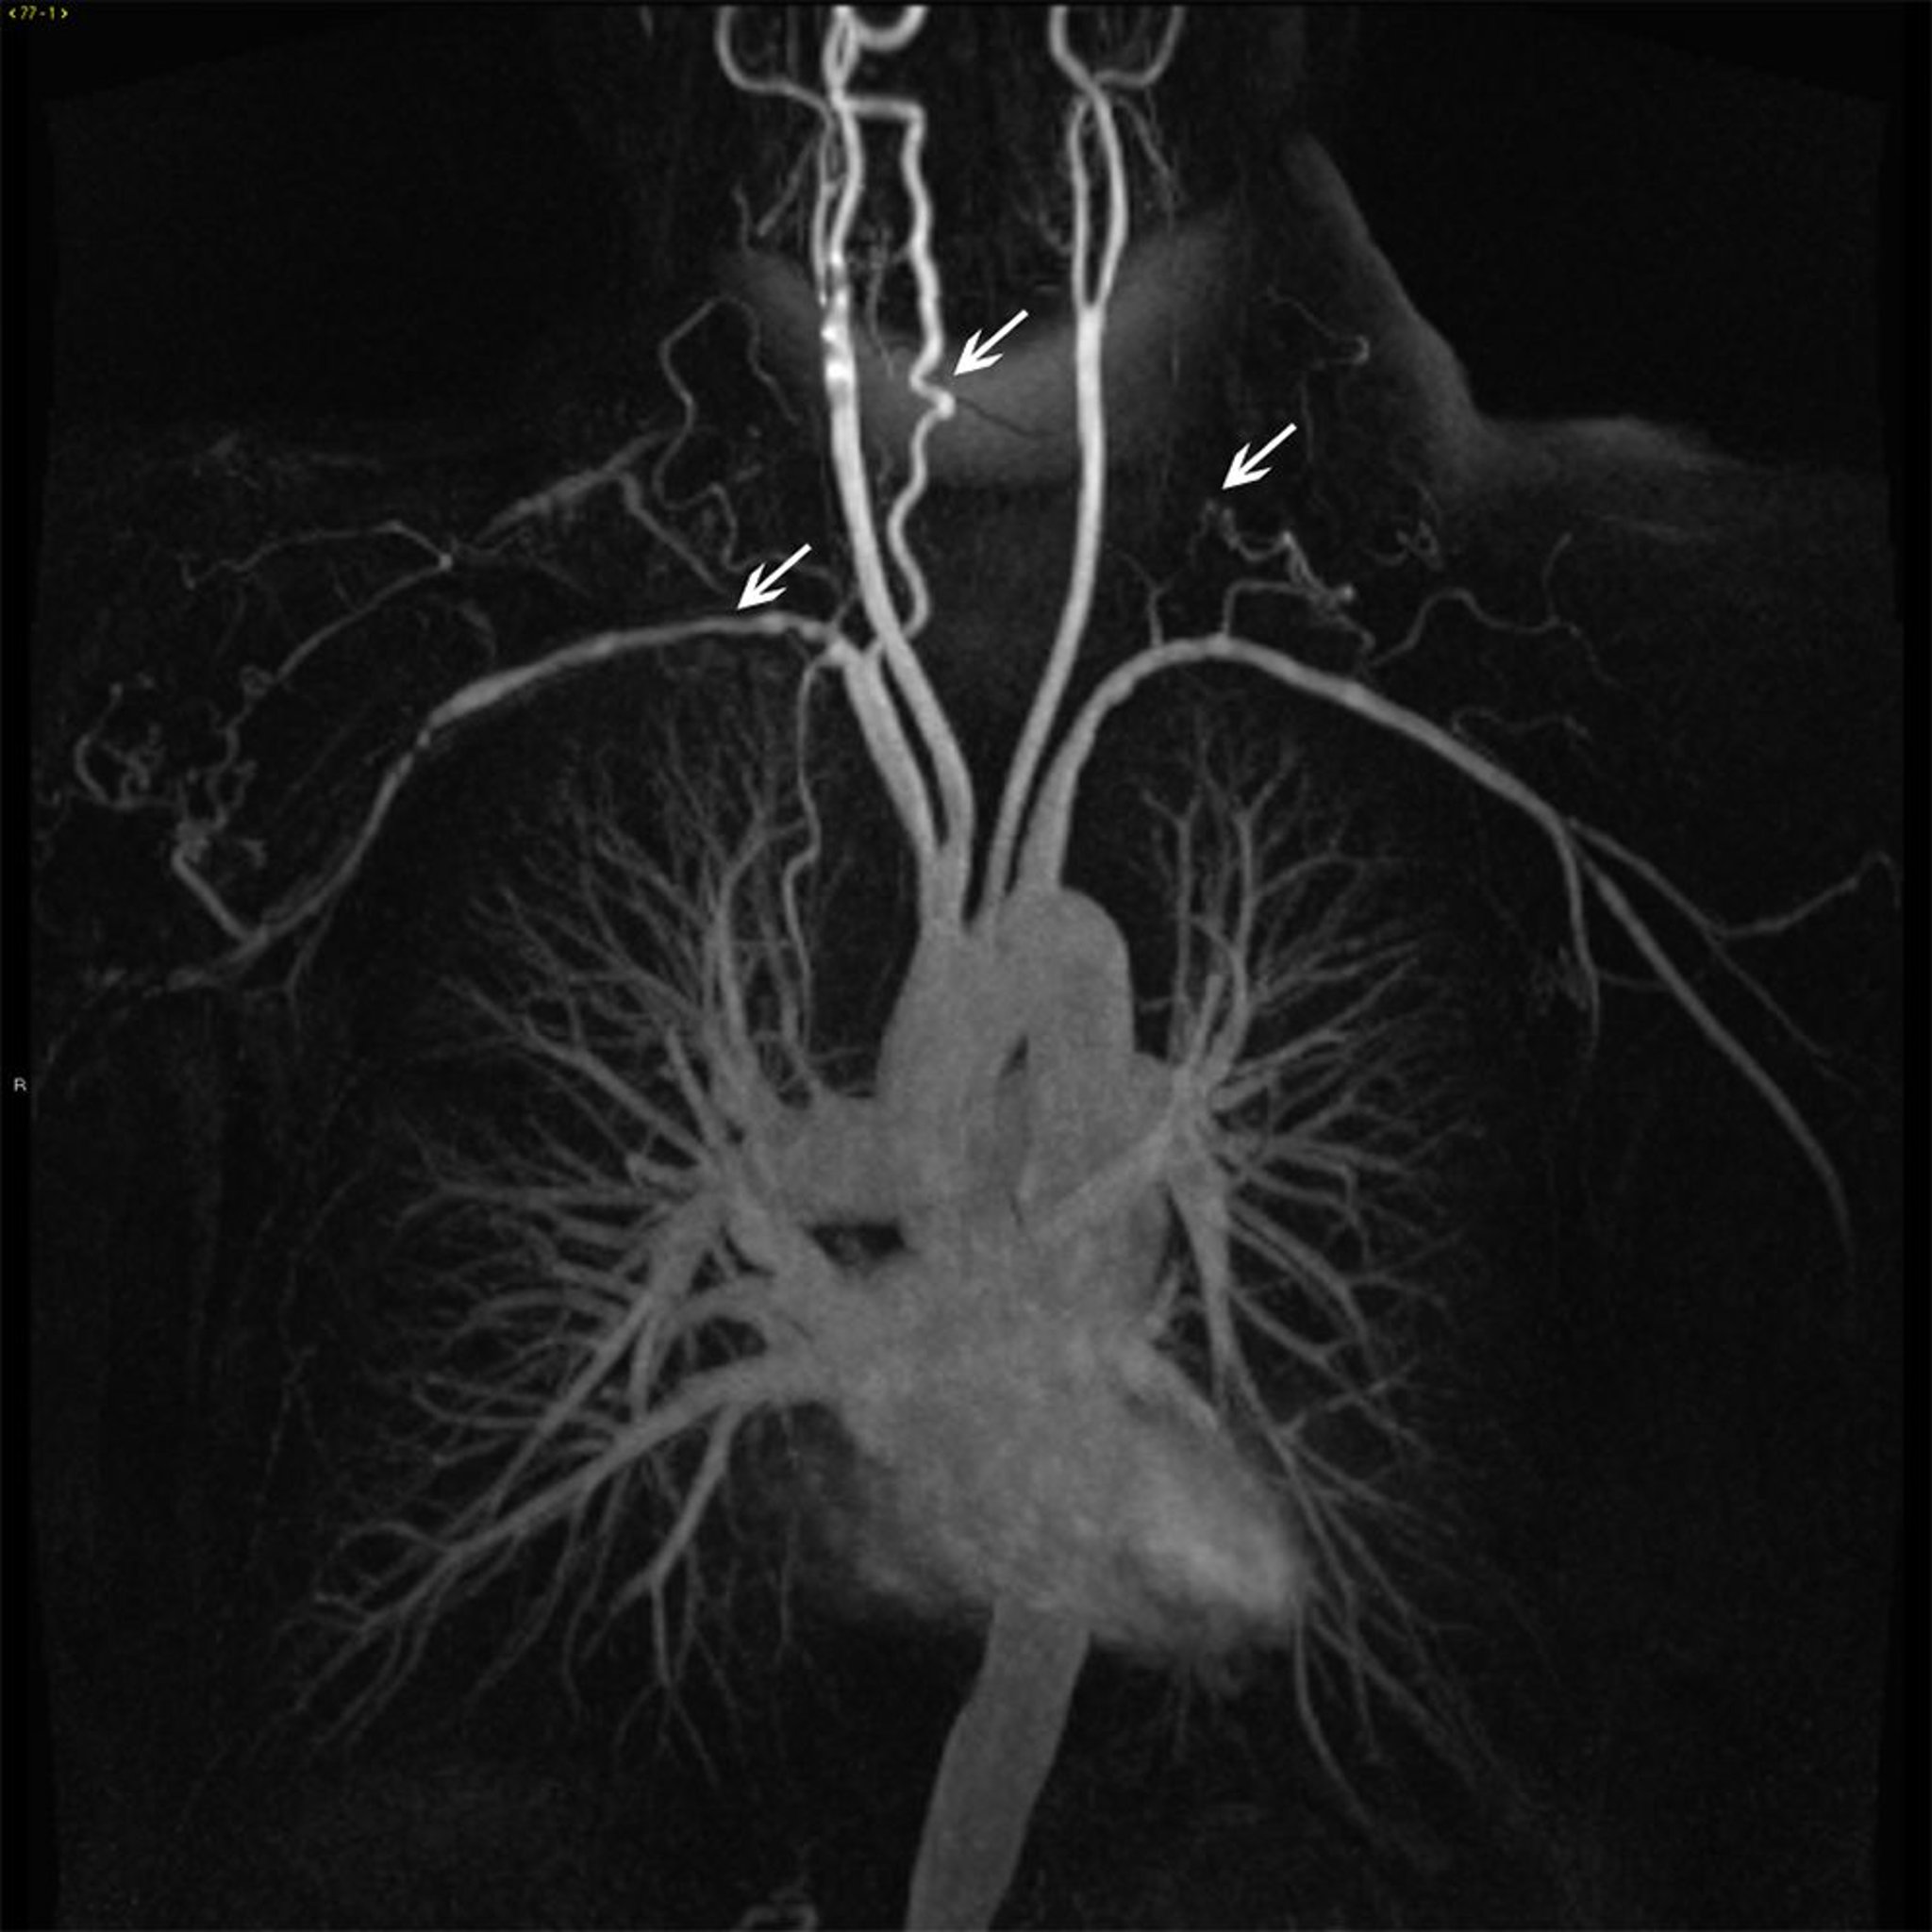

Ramas de aorta torácica ascendente en un paciente con arteritis de Takayasu

Esta imagen muestra irregularidad y estrechamiento mural (flechas blancas) en varias ramas de la aorta ascendente.